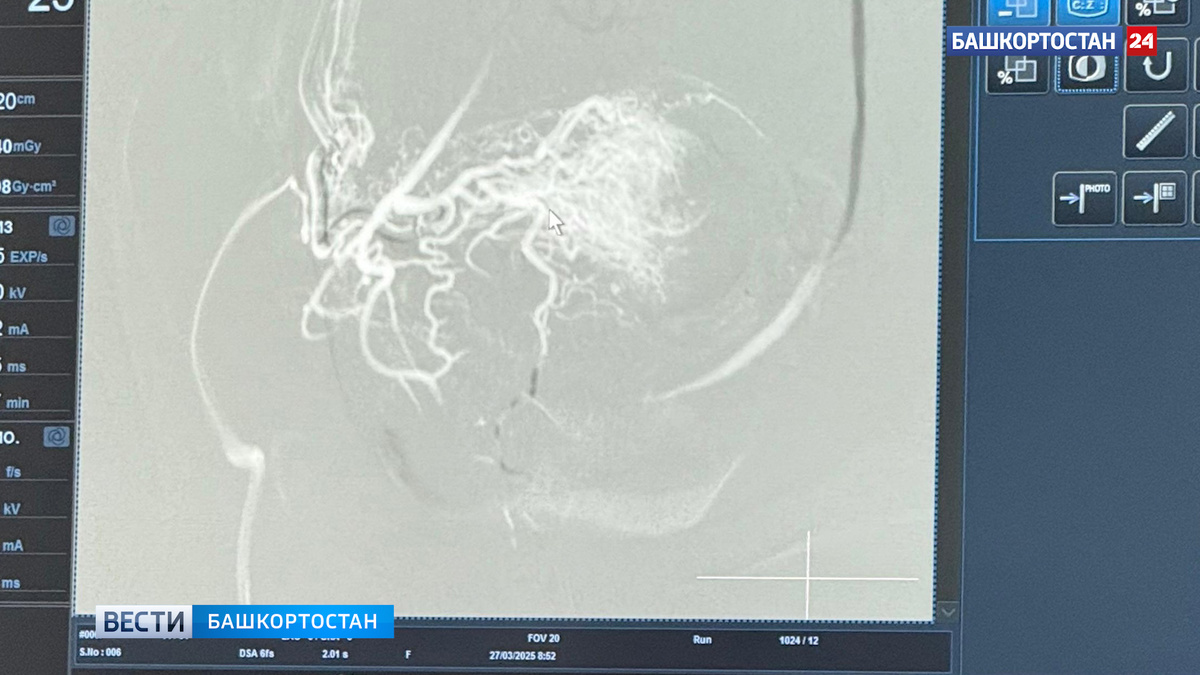

На консилиуме было решено провести оперативное лечение с сохранением репродуктивной функции. На первом этапе врачи выполнили эмболизацию маточных артерий, чтобы минимизировать риски кровотечения. Второй этап – удаление плодного яйца.